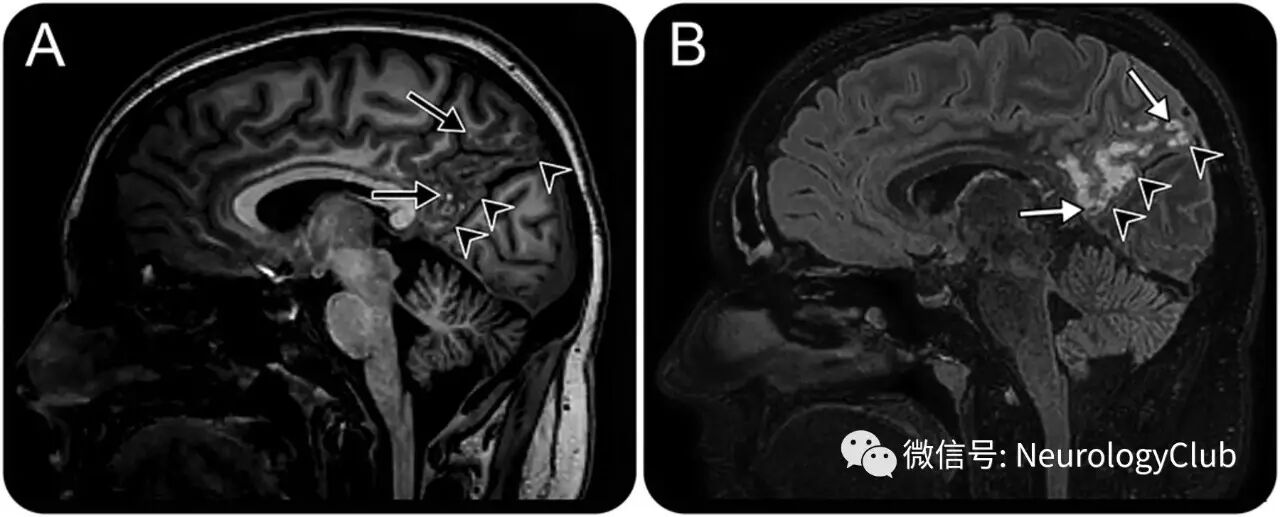

31岁女性,表现为慢性头痛。MRI提示右侧不典型顶叶病变,累及深部皮质带和邻近的浅表皮质下白质(图1,2)。注射对比剂后病灶无强化。弥散加权成像,磁敏感加权成像和动态磁敏感对比增强未见信号异常。

(图1:A:T1WI;B:FLAIR;右侧顶叶病变累及深部皮质带和邻近皮质下白质[箭头],分散成小的接合的结节,FLAIR上为高信号,T1WI上为低信号伴点状高信号[黑箭],为MVNT的影像学特征;一些病灶FLAIR上表现为中央低信号[白箭])